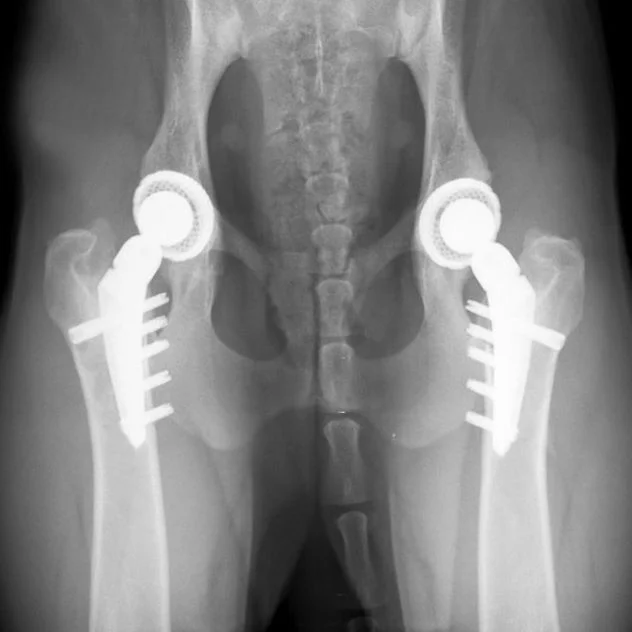

Joint Solutions